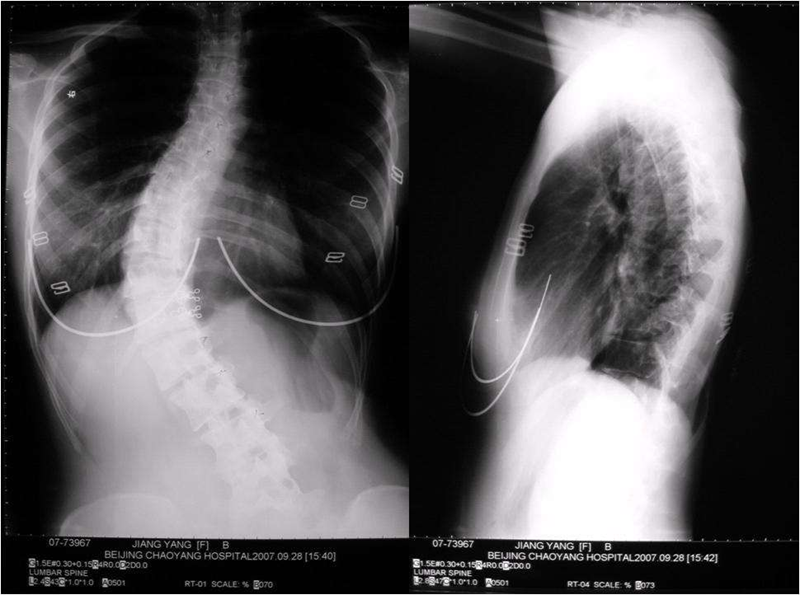

當人體的脊柱在側面觀察時,理應是一條直線。然而,如果這條線彎曲了,我們稱之為脊柱側彎。這一狀況可能給患者帶來不僅是外觀上的困擾,更有可能影響到身體的健康和機能。那么,如何判斷自己或他人是否患有脊柱側彎呢?下面將介紹一些通俗易懂的判斷方法

脊柱側彎是一種常見的骨骼問題,它通常在青少年時期被發現,并可能伴隨個體成長。然而,很多人對脊柱側彎的嚴重性感到困惑,尤其是對于那些尚未出現明顯癥狀的人。在這篇文章中,我們將探討脊柱側彎的嚴重性,并提供一些基本的指導和建議